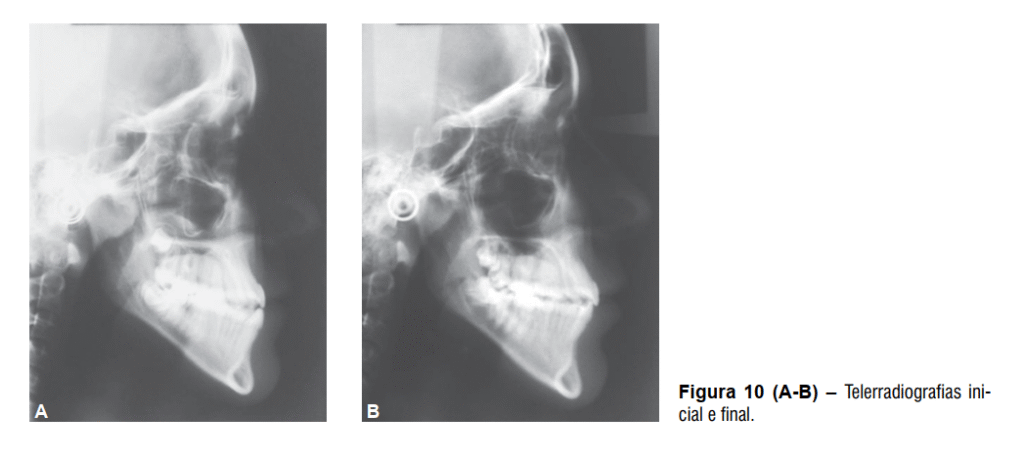

Após a remoção do aparelho fixo foi instalada como contenção uma placa de Hawley superior, 3×3 inferior e uso noturno de mentoneira com finalidade de restringir o crescimento mandibular. O tratamento proposto possibilitou a correção da discrepância transversal e da relação anteroposterior de forma satisfatória, melhorando o perímetro do arco e obtendo-se uma relação molar de Classe I (Figura 8 A-E), além da melhora significativa do perfil facial e estética mais agradável (Figura 9 A-B). As telerradiografias inicial e final mostram a melhora da relação entre as bases ósseas (Figura 10) juntamente com a sobreposição dos cefalogramas (Figura 11).

O componente esquelético da maxila não apresentou grandes alterações, entretanto, a mandíbula teve significante crescimento representado pela variável CoGn. Também houve suave aumento das variáveis que representam o padrão da face no sentido vertical, com destaque para a alteração sofrida pela variável AFAI, que teve aumento de 4,1 mm (Tabela 1).

O componente dentoalveolar da maxila apresentou maiores alterações, assim como já era esperado. Os incisivos superiores apresentaram vestibularização e protrusão enquanto os molares superiores apresentaram mesialização com angulação da sua coroa para a mesial (Tabela 1). O componente dentoalveolar inferior apresentou suaves alterações, principalmente em relação à extrusão sofrida pelos incisivos inferiores (Tabela 1).

Na relação entre os dentes superiores e inferiores houve grande melhora representada pelas variáveis:

relação molar, trespasse horizontal e trespasse vertical (Tabela 1), assim como houve visível melhora em relação ao perfil facial, que ao final do tratamento se apresentava menos côncavo (Tabela 1)